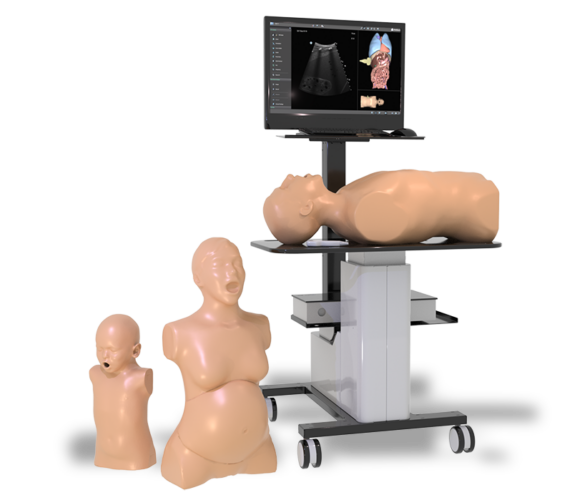

Simbionix Ultrasound Mentor is the answer to the growing need for ultrasound training among multiple medical specialties. This modular simulation platform enables easy manikin rotation (male, female, pediatric and interventional), and offers diverse applications for a range of specialties such as OB/GYN, Point-of-care Ultrasound (POCUS) and Echocardiography.

Ultrasound Mentor accelerates the development of basic to advanced technical and cognitive skills, by providing not only the probe manipulation training, but also a didactic environment enabling structured, self-guided learning including step-by-step instructions and educational aids such as 3D anatomical map and probe positioning assistant, all backed up with our progress monitoring tool MentorLearn.

- A modular platform with easy manikin rotation